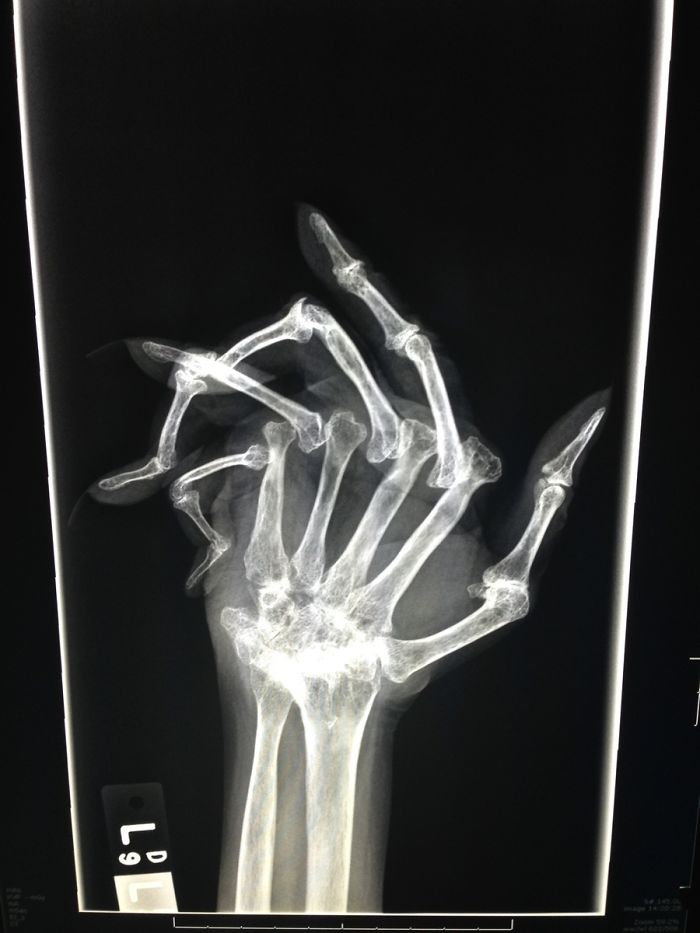

Advanced Rheumatoid Arthritis

My daughter was diagnosed with RA when she was 13. She is 29 now and has had three surgeries to improve her joints to help her be able to walk. Her toes looked much like this X-ray. This is a horrible illness that is invisible until it is at this point. The pain that these patients deal with every day is heartbreaking. People still give her dirty looks when she uses a handicap parking space. Imagine if your toes looked like this...don't you think you would want to walk as little as possible?

The Worst Case Of Rheumatoid Arthritis I've Ever Seen